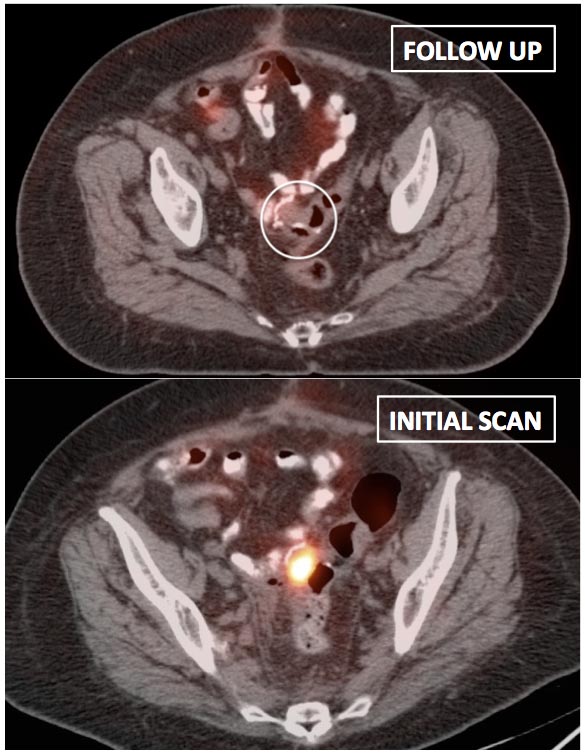

• A solitary focus of intense uptake presents in an otherwise non-avid (or minimally avid) colon.  Although this focal uptake may still represent normal physiologic uptake, it is reasonable to raise the possibility of a small polyp and recommend colonoscopy (polyps are rarely visible on the CT images).

We generally report, “As an adenomatous polyp or other pathology cannot be excluded, further evaluation with colonoscopy may be warranted, if not recently performed.”